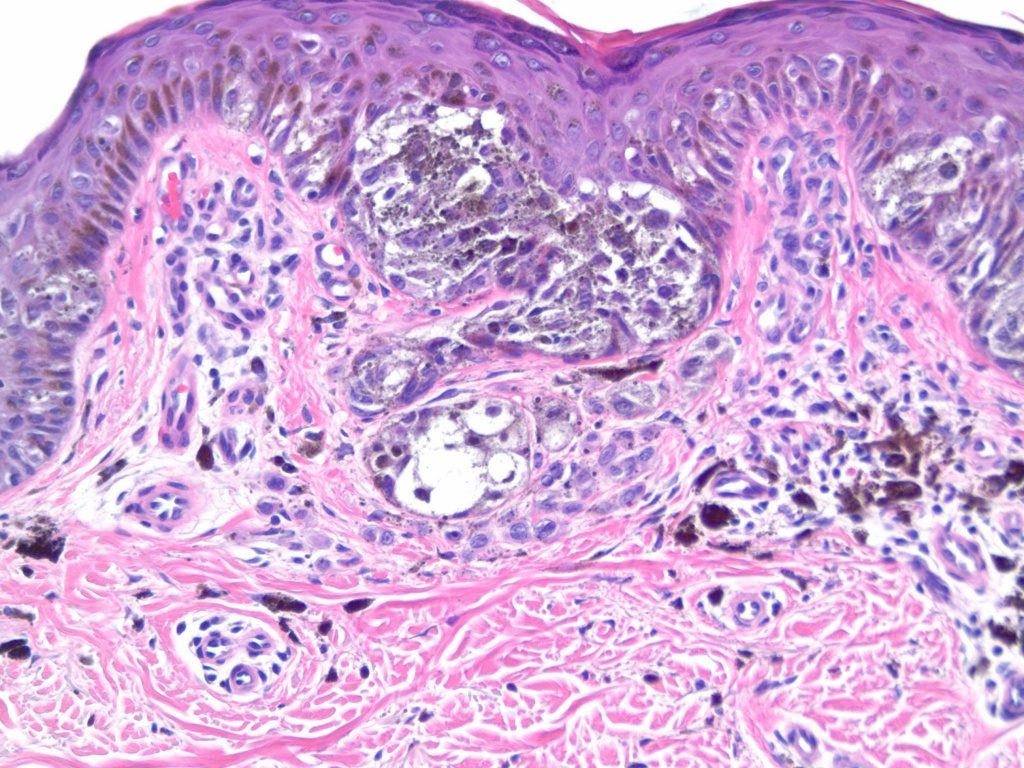

Ученые из Медицинского исследовательского института Стэнфорд-Бернхам (США) выяснили, что даже если лактатдегидрогеназа А исключена из метаболизма клетки опухоли кожи (меланомы), через некоторое время гликолиз возобновляется — и раковая клетка снова получает энергию, растет и делится. Медики также установили, что на замену LDHA приходит другое вещество — фактор транскрипции ATF4: мутантная клетка вскоре переключается на сигнальный путь с участием этого вещества и возобновляет жизнедеятельность.

После того как ученые блокировали LDHA в клетках меланомы, последние перестали использовать АТФ в качестве источника энергии: вместо этого они начали «поедать» аминокислоту глутамин. При этом в клетках заметно увеличилось производство ATF4, благодаря которому возрастало поступление глутамина в клетку извне. Приток аминокислот, в свою очередь, активировал выработку фермента mTOR — регулятора клеточного роста и выживания, благодаря чему клетки продолжали расти.